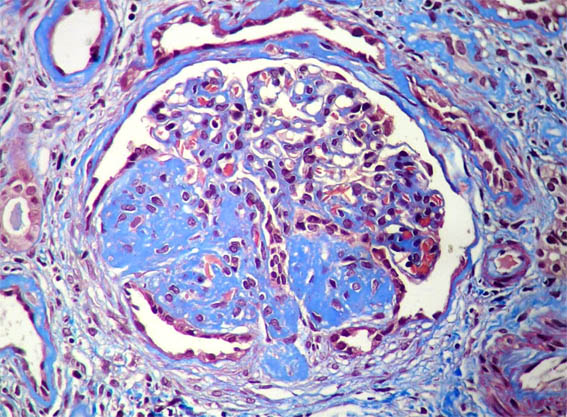

Figure 8.

Methenamine-silver

stain, X400.